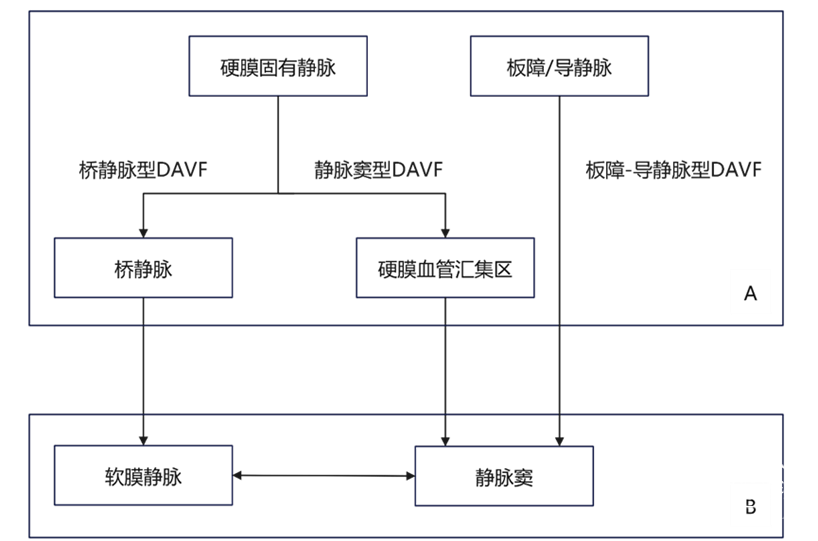

DAVF的动-静脉移行结构可以发生在硬膜固有静脉和骨内静脉的任何部位,随后指向两个不同的引流方向:即桥静脉和静脉窦,形成了三种规律性引流模式(图1)。基于该静脉血管构筑,以解构和定位DAVF精准治疗的靶区为切入点,本中心提出DAVF新的形态学分型。依据引流节点在选择性造影中的显影顺序分为三型。

注:A为DAVF的精准栓塞靶区,B为下游引流结构

图1. 硬脑膜动静脉瘘(DAVF)三种分型的引流模式与治疗靶区